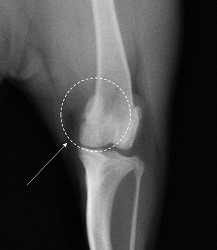

この膝蓋骨が正常な位置から外れ、内側にずれる状態を膝蓋骨内方脱臼(Medial Patellar Luxation, MPL)と言います。外側にずれる場合は膝蓋骨外方脱臼と呼びます。

グレード1: 普段は膝蓋骨が滑車溝に入っているが、手で押すと外れる状態。

グレード2: 自然に脱臼するが、手で簡単に元の位置に戻せる、または自然に戻る状態。

グレード3: 常に膝蓋骨が外れているが、手で元の位置に戻すことができる。ただし、すぐに再び外れてしまう。

グレード4: 常に外れている状態で、手で押しても元の位置に戻すことができない状態。